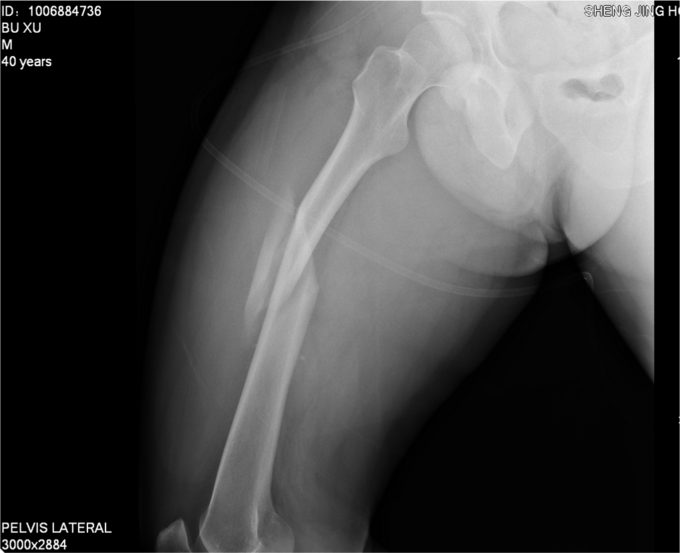

患者于2014-8-14 13:30左右,工作时不慎被重物砸伤,当时无法站立,自觉头晕,意识清楚,自觉大腿部疼痛,无法活动,被急送往我院急诊,经检查诊断为“右股骨干骨折”,给予对症处置,并请我科会诊,现患者为进一步诊治,转入我科病房,我科以“右股骨干骨折”为诊断收入院,患者伤后无昏迷,无恶心呕吐,无呼吸困难,至今未排便排气

右大腿肿胀,活动受限,压痛(+),骨擦音(+),骨擦感(+),可见异常活动,患肢皮肤感觉较健侧未见明显异常;足趾活动灵活,肌力正常,末梢循环可,足背动脉可触及。

诊断:右股骨干骨折 患者入院后急诊行右胫骨结节骨骼牵引术,术后维持患者长度,减轻患者疼痛,完善相关检查后,行右股骨干骨折闭合复位髓内针内固定术。